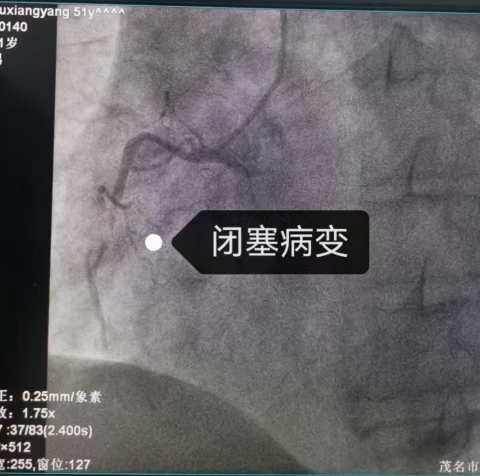

25分鐘的轉(zhuǎn)運(yùn)途中,患者一度煩躁把氣管插管都拔掉了。我院胸痛中心團(tuán)隊(duì)已經(jīng)激活導(dǎo)管室等候患者并做好了各方面準(zhǔn)備,到達(dá)醫(yī)院時(shí),病情再次惡化。我院多學(xué)科團(tuán)隊(duì)(包括麻醉科、急診科、重癥醫(yī)學(xué)科和心內(nèi)科)立即展開(kāi)聯(lián)合救治。經(jīng)過(guò)十余次除顫、緊急應(yīng)用硫酸鎂等靜脈用藥等搶救措施,很快通過(guò)急診冠脈介入手術(shù)成功開(kāi)通閉塞血管,患者心律逐漸穩(wěn)定。后續(xù)經(jīng)過(guò)重癥監(jiān)護(hù)室和心內(nèi)科的精心治療,老許最終康復(fù)出院,與家人團(tuán)聚。